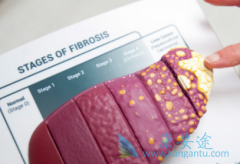

慢性丙型肝炎是一种严重的病毒性肝炎疾病,没有及时治疗很有可能会导致患者出现肝硬化和肝癌的情况。好在丙肝在现在并不是什么难治的疾病,接受吉三代这类抗丙肝病毒治疗药物的治疗一般在一个疗程内就可以实现完全治愈,丙肝抗体转阴,那么 丙肝抗体 已 ...